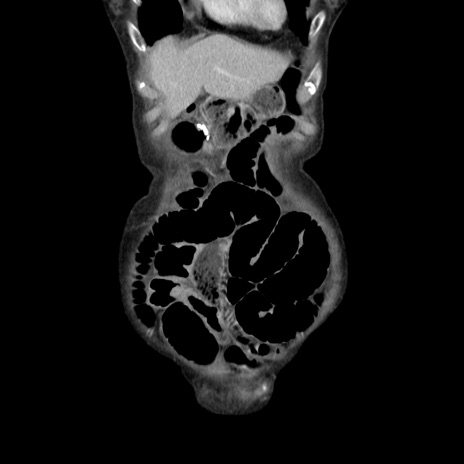

横断像

【症例】80歳代女性

【現病歴】約9時間前に食後から胸のつかえた感じあり、嘔吐あり、来院。

【既往歴】胃癌(全摘)、胆摘、虫垂炎